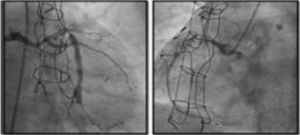

DeviceThe only coronary sinus reducer device currently available and approved for clinical use is the Neovasc Reducer™ (Neovasc Inc., Richmond, BC, Canada). The device consists of a stainless steel mesh mounted in an hourglass-shaped balloon, which after inflation adapts to the tapering conformation of the coronary sinus with two asymmetrical extremities (the proximal larger than the distal) and a narrow central portion that following endothelialization (which takes 4–6 weeks) creates a pressure gradient between the venous circulation corresponding to the territory of the left coronary artery and the right atrium. The semicompliant balloon is available in only one size and the device’s final expanded diameters (9−14 mm) are dependent on the filling pressure, enabling it to adapt to fit the range of anatomies encountered in most patients, while the diameter of the central neck will always be 3 mm (Figure 3).

The device is implanted with a 10-20% oversizing -20 at each end relative to the coronary sinus diameter, in order to anchor the device and to trigger the vascular injury that will induce tissue regrowth and endothelialization.

After implantation, the device can be balloon expanded at any time, so that further interventions can be performed through the coronary sinus if required.